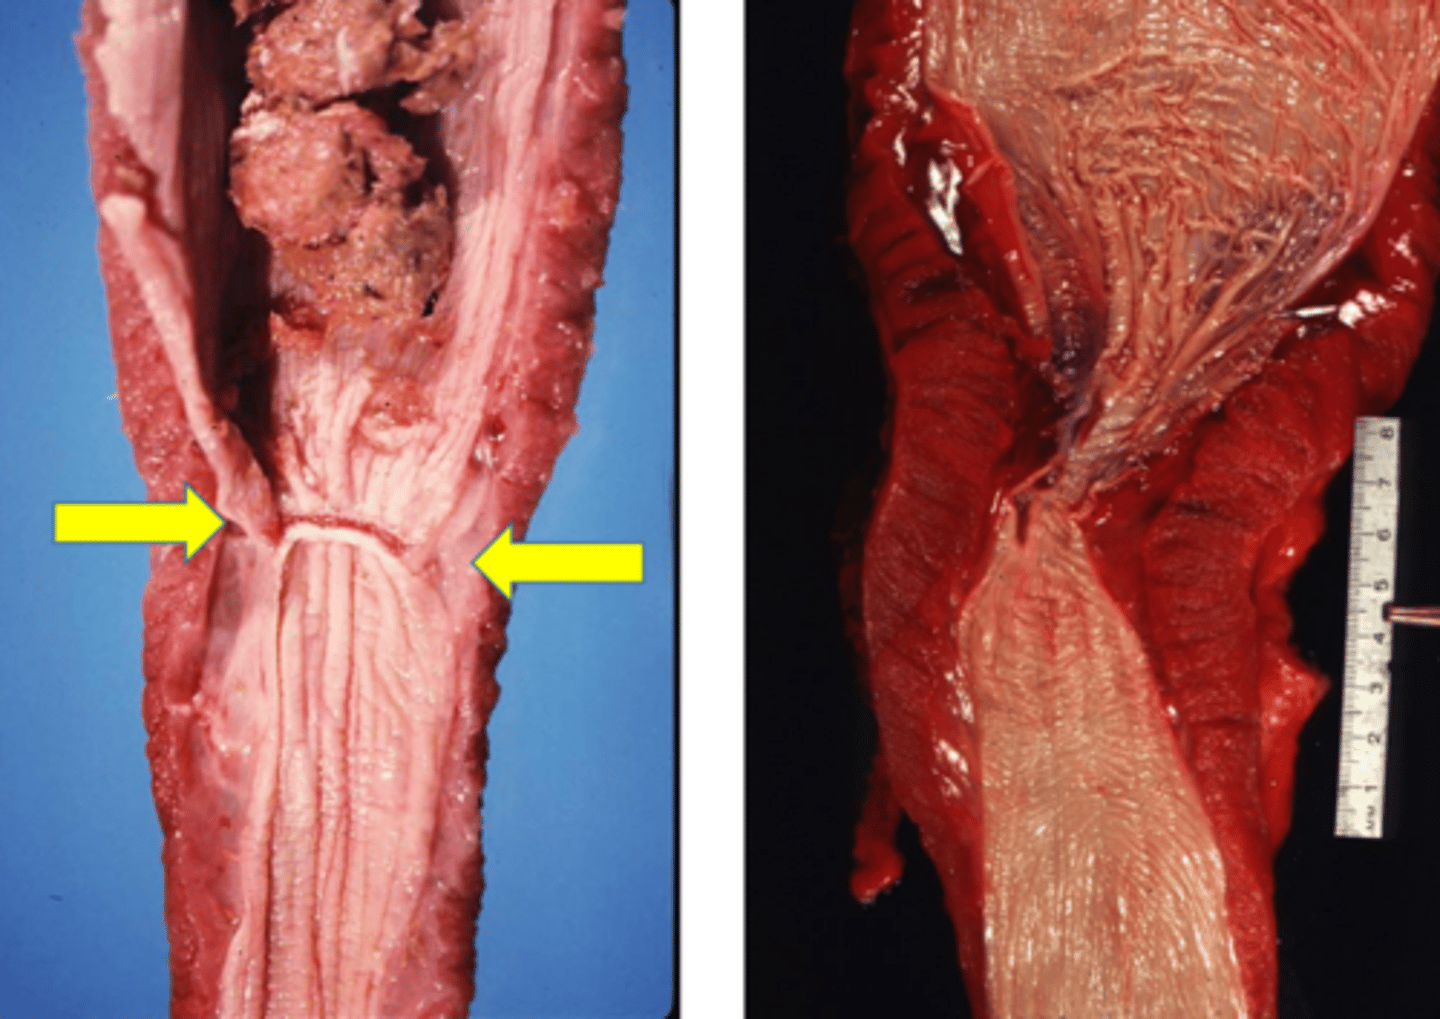

Identify the pathology?

Bloat - (arrow pointing to bloat line where congestion is showing)